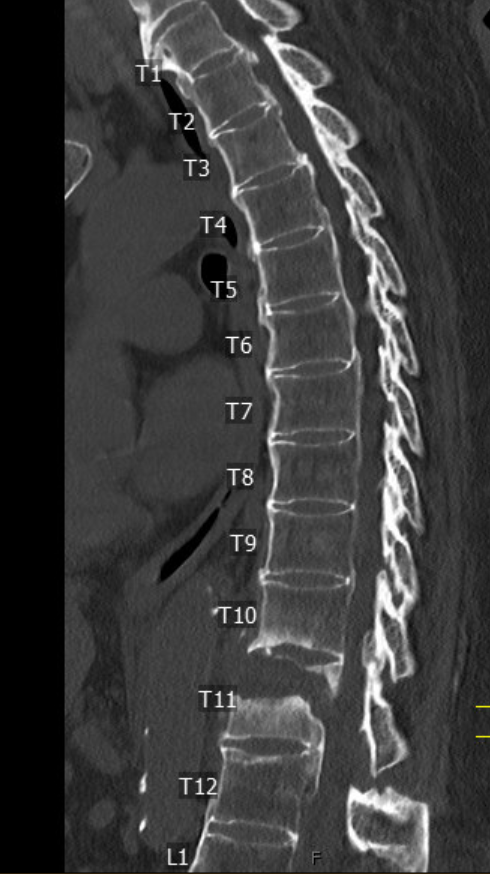

Additional patient with "bamboo spine" and T11 "chalk stick fracture".